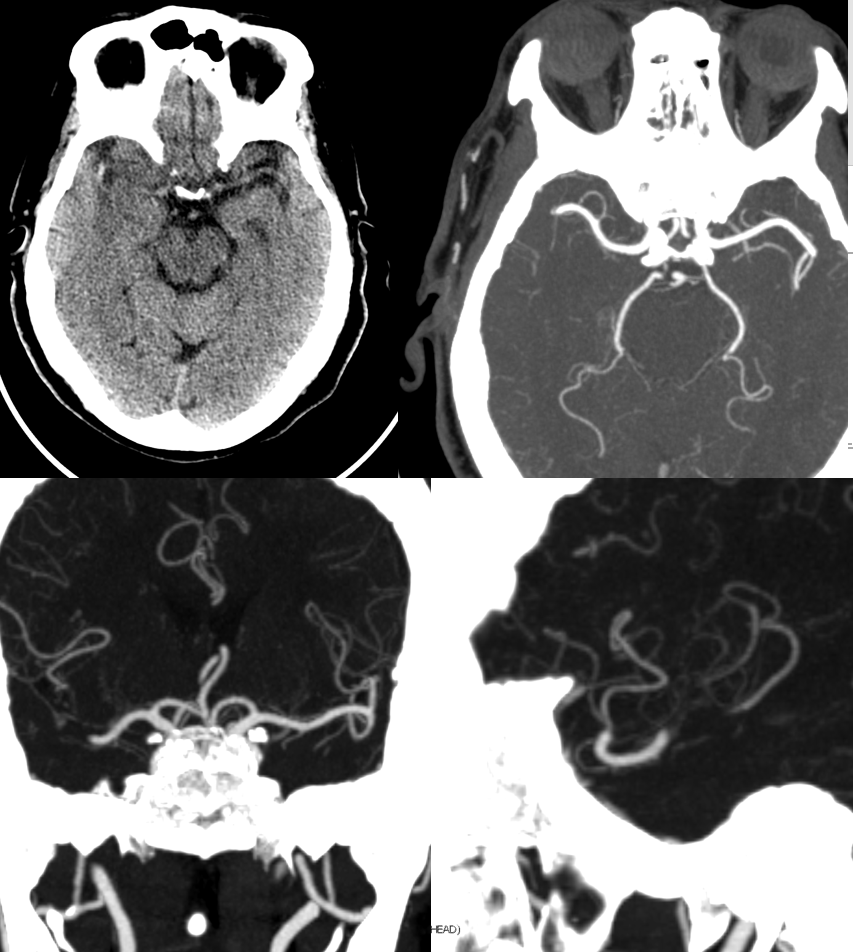

This is correctly billed as a proximal right M2 occlusion. Dense MCA sign on right.

Perfusion

Angio